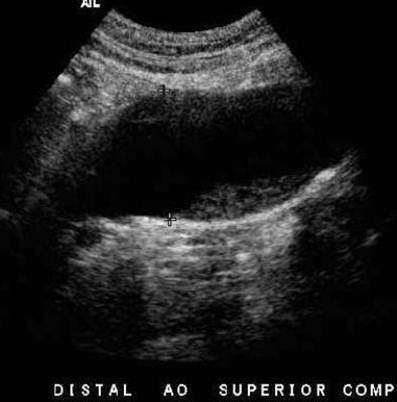

AO:

Proximal aorta

High systolic peak

Low diastolic comp.

Clean window